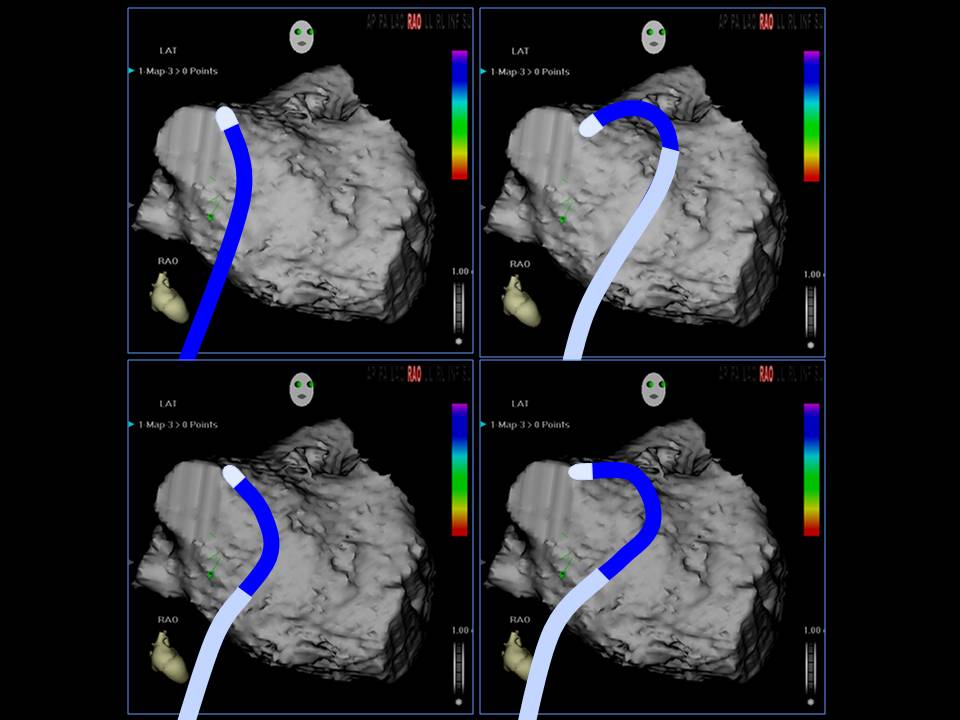

肺静脉隔离术难点

董建增